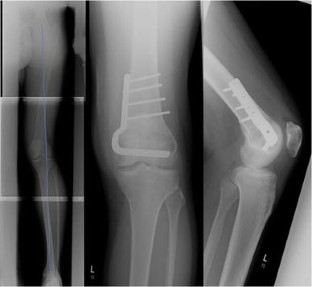

Fig. 1

Fig. 2

Fig. 3

Fig. 4